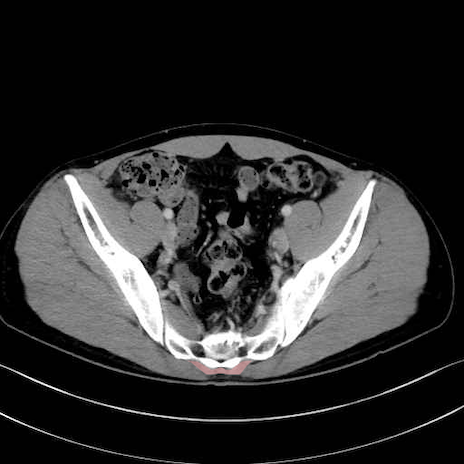

肛門挙筋 (Levator ani)